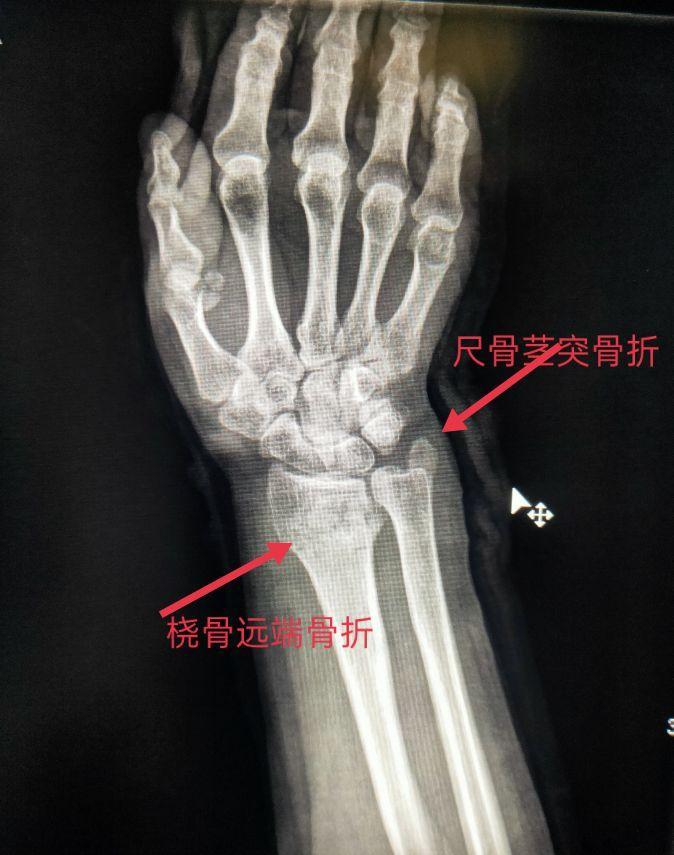

四、尺、桡骨骨折X线片

尺骨桡骨骨折以桡骨远端骨折多见。其次是尺骨桡骨双骨折,多发生于青少年。